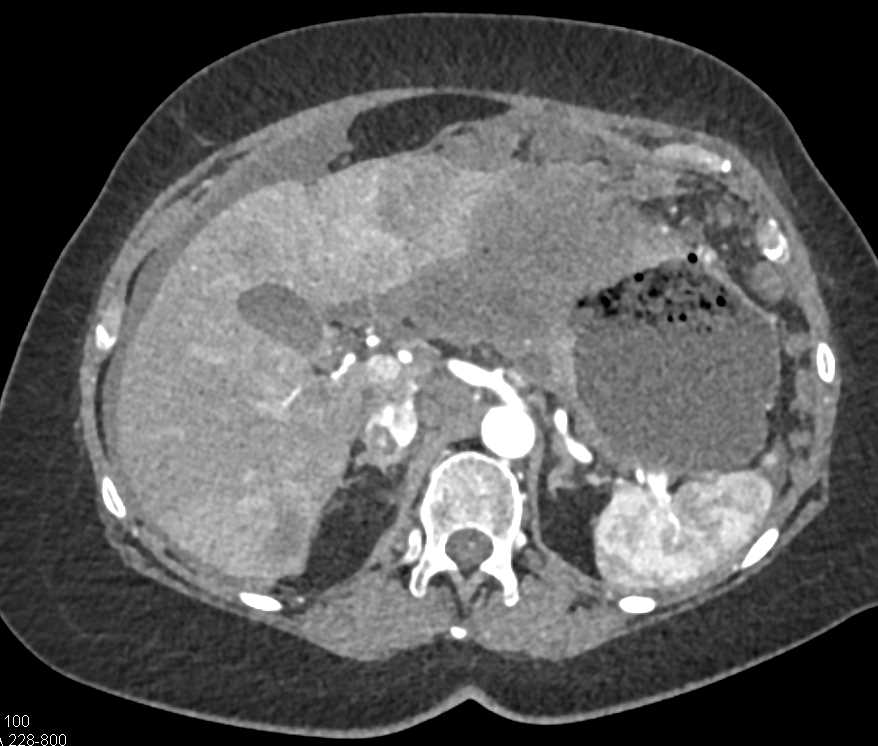

Biloma with Active Bleed